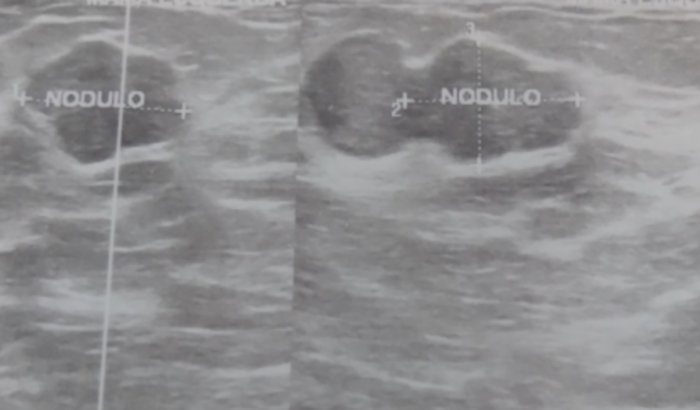

Eu sou Edna criei essa vakinha pra fazer uma cirurgia de fibroadenoma que é um tumor benigno que precisa ser retirado com urgência e custa R$15000 e não tenho condições de arcar com todos os custos e no sus não consegui nada já faz 5 meses que estou tentando por o encaminhamento pra cirurgia de emergência